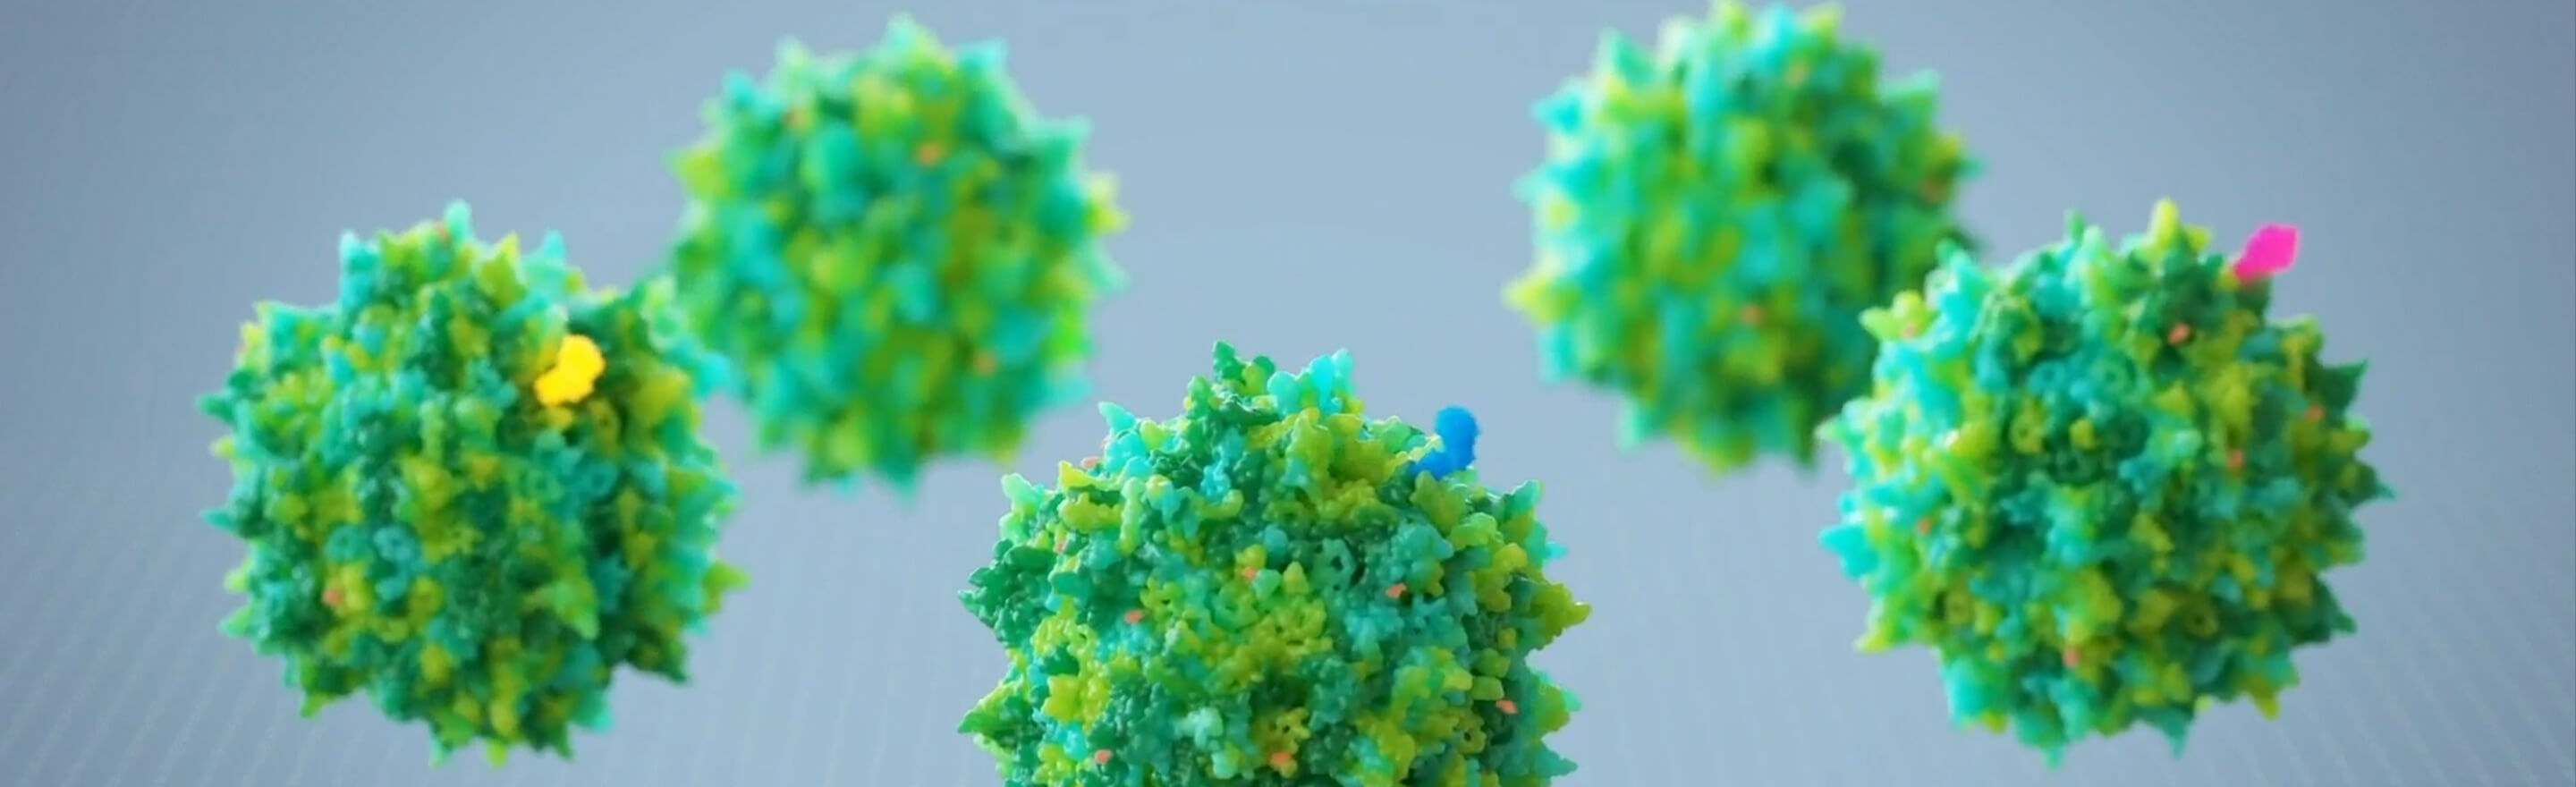

JUST-AAV is JCR’s proprietary gene therapy platform based on adeno-associated virus (AAV), with the potential to be applied to a wide range of diseases.

by modifying the tag (binder or miniaturized antibody)

expressed on the AAV capsid surface.

JUST-AAV is JCR’s proprietary engineered AAV. A miniaturized antibody displayed on the capsid surface helps direct the vector efficiently to target tissues and organs. With promising non-clinical results, JCR has succeeded in reducing liver accumulation by modifying part of the gene that encodes the capsid. Together, these approaches are expected to reduce liver toxicity risk while enhancing therapeutic gene expression in target tissues and organs.